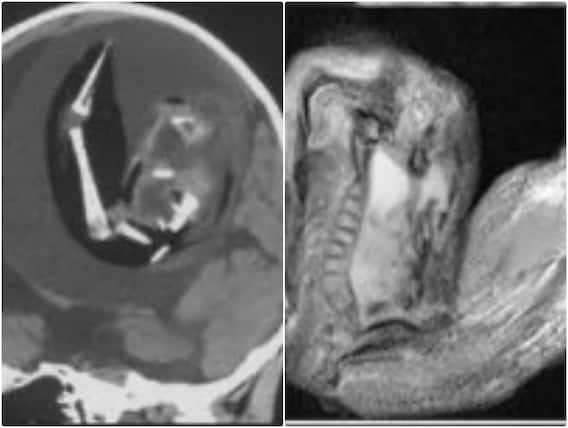

चीन में न्यूरोलॉजी जर्नल में प्रकाशित एक खबर के मुताबिक बताया गया है कि चीन में एक साल पहले पैदा होने वाली बच्ची के दिमाग के अंदर से एक भ्रूण को निकाला गया है. बताया जा रहा है कि जन्म लेने के बाद बच्ची के दिमाग का साइज काफी तेजी से बढ़ रहा था. जिससे परेशान उसके माता-पिता उसे इलाज के लिए अस्पताल लेकर पहुंचे. जहां उस बच्ची के दिमाग का सिटी स्कैन किया गया तो इस राज से पर्दा खुल गया.

बच्ची के दिमाग की सिटी स्कैन की रिपोर्ट की जांच करने पर डॉक्टर्स ने उसके दिमाग में एक भ्रूण को पाया. जिसे देख डॉक्टर्स की टीम हैरत में पड़ गई. एक रिपोर्ट के अनुसार डॉक्टर्स ने बताया कि बच्ची के दिमाग के अंदर भ्रूण तकरीबन 4 इंच तक बढ़ गया था. जहां उसकी कमर की हड्डियों और उंगलियों के नाखूनों का विकास हो गया था. फिलहाल एक लंबे और सफल ऑपरेशन के बाद बच्ची के दिमाग से उस भ्रूण को बच्ची के दिमाग से बाहर निकाला जा चुका है.